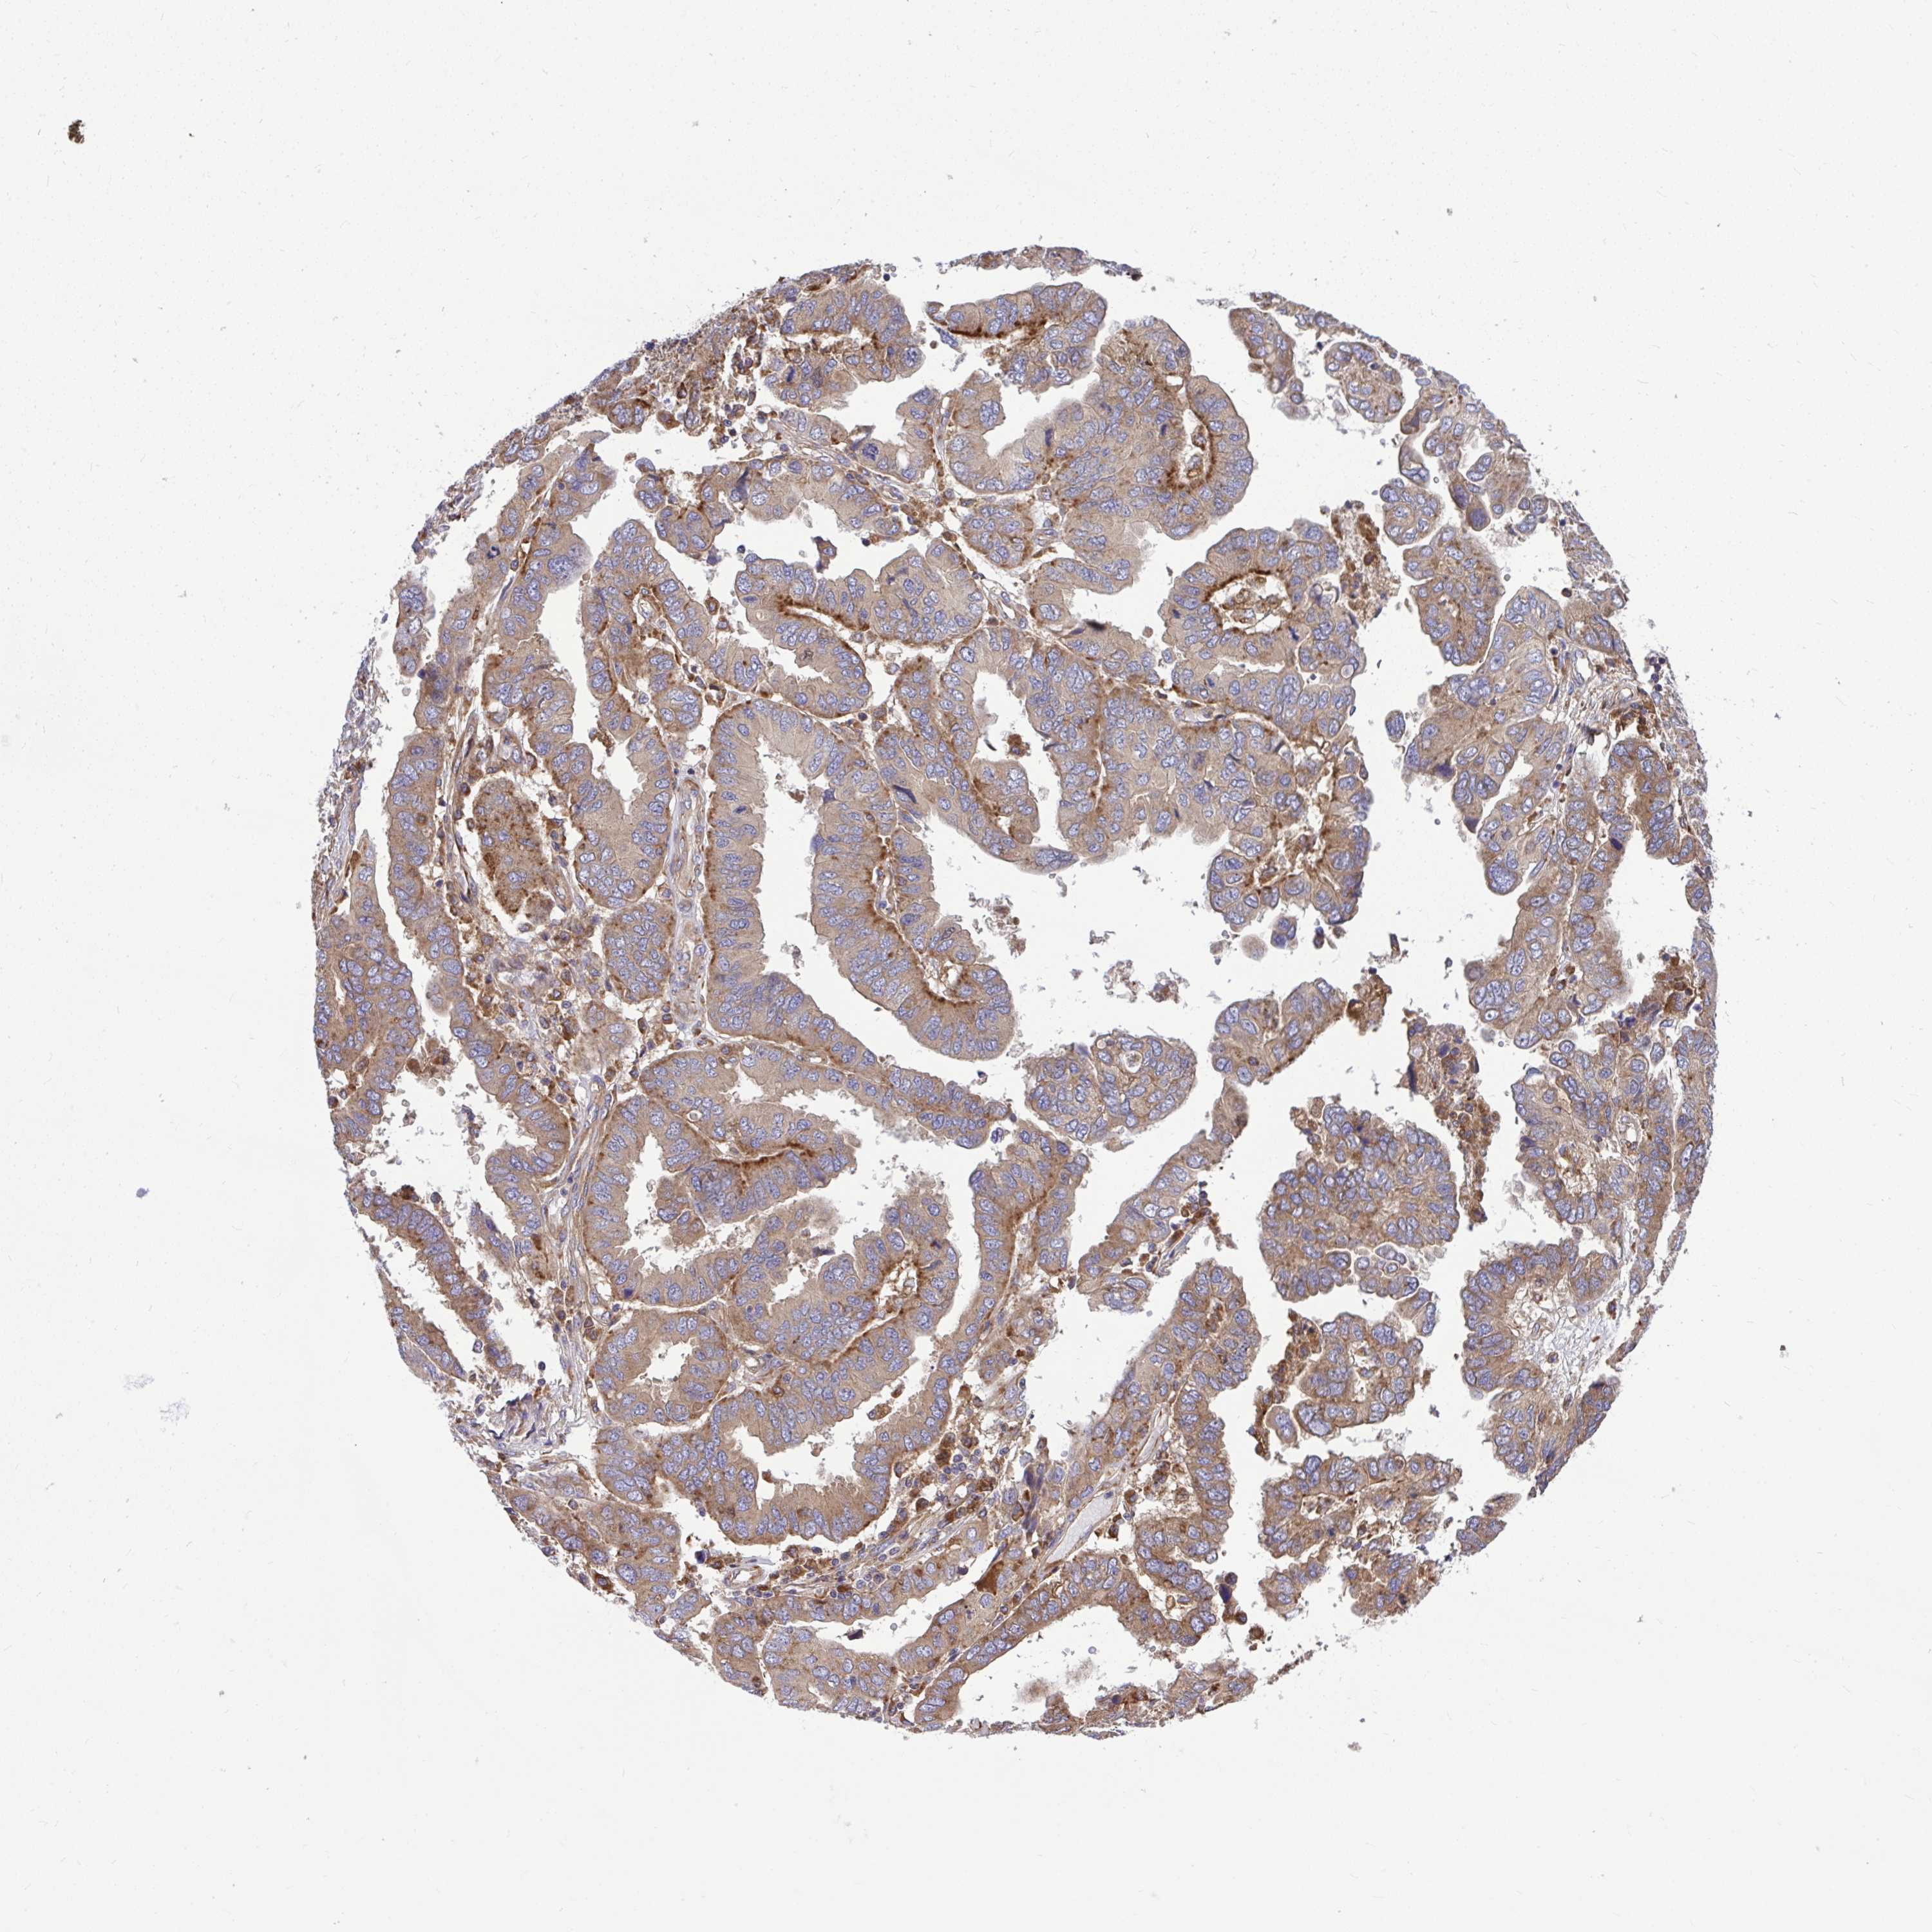

OVARIAN CANCER - Protein expressioni

A mouse-over function shows sample information and annotation data. Click on an image to view it in a full screen mode. Samples can be filtered based on level of antibody staining by selecting one or several of the following categories: high, medium, low and not detected. The assay and annotation is described here.

Note that samples used for immunohistochemistry by the Human Protein Atlas do not correspond to samples in the TCGA dataset.

Antibody stainingi

Antibody staining in the annotated cell types in the current human tissue is reported as not detected, low, medium, or high, based on conventional immunohistochemistry profiling in selected tissues. This score is based on the combination of the staining intensity and fraction of stained cells.

Each image is clickable and will lead to virtual microscopy that enables deeper exploration of all samples and also displays staining intensity scores, fraction scores and subcellular localization as well as patient and tissue information for each sample.

Antibody HPA035945

Antibody HPA056766

Antibody CAB037212

Cystadenocarcinoma, serous, NOS

Carcinoma, endometroid

Cystadenocarcinoma, mucinous, NOS

Carcinoma, NOS